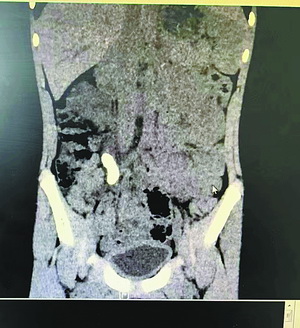

小伟的输尿管结石在CT下显得触目惊心。厦门市海沧医院 供图

检查结果令人大吃一惊:小伟患的是肾多发结石合并输尿管结石,输尿管结石直径足有3.3厘米,被撑得相当于成人两个手指宽,且结石已嵌顿,导致肾脏中重度积水,必须尽快手术把结石取出来。